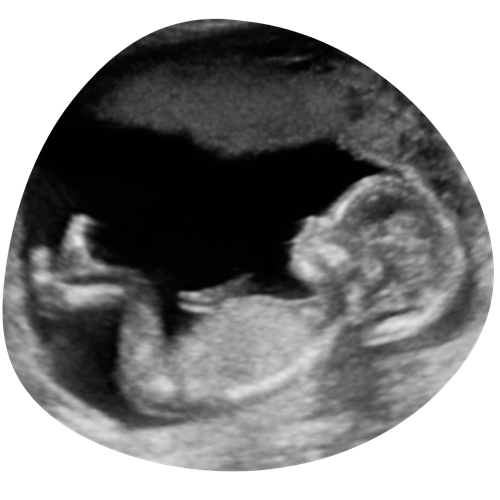

3/4D echo

Een bijzondere echo waarbij jouw ongeboren kind haarscherp en realistisch in beeld wordt gebracht. Je ziet niet alleen de contouren, maar ook het volume van je baby. Heeft hij/zij bolle wangetjes en op wie lijkt hij/zij eigenlijk? Soms zie je ook echt al de mimiek tijdens de echo: boos kijken, lachen, pruilen of even gapen…

€90 (30 minuten)